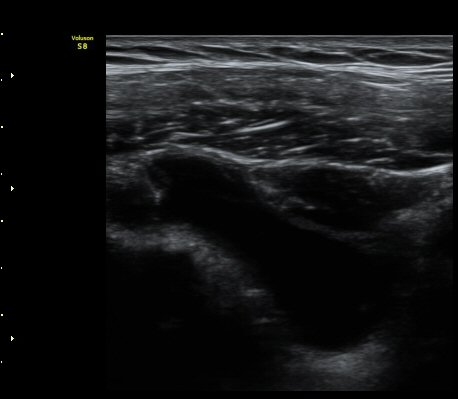

ÃÊÀ½ÆÄ °Ë»ç

2049205267_d18eca99_IMG_20140331_2_1-c.jpg